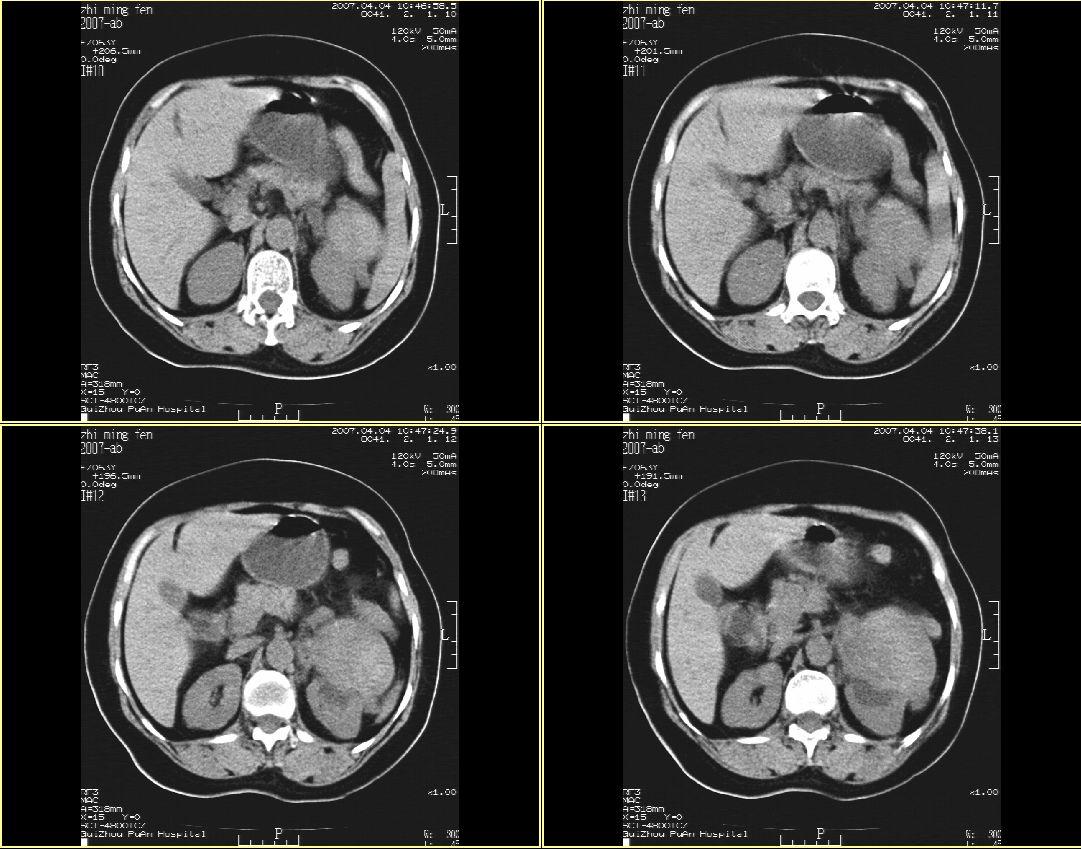

以下是引用hhcckk在2007-4-9 9:18:00的发言:[br]我认为就是一个病灶,病灶上端密度较均匀,下方有明显的钙化,部分呈不完全的环状,考虑肾癌[br]1、肾癌的特征性ct表现为肾实质的占位,局部隆起外突[br]2、肿瘤内的钙化常见,多发生在肿瘤内部,也可以在肿瘤周边呈弧型或不完全的环行钙化[br]3、最常见的三大症状,血尿,腰痛,包块此病人也较符合,增强吧

以下是引用swyyy2007在2007-4-9 18:42:00的发言:[br]支持左肾癌累及肾窦肾盂,左肾积水 [br] [br]